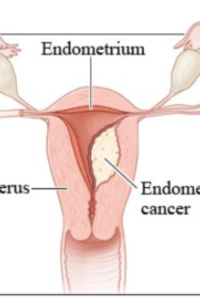

Uterine Cancer

Uterine Cancer – usually presents with heavy irregular vaginal bleeding. Hence it is usually diagnosed in early stages. But there does exist a pre-cancerous condition which is called Endometrial Hyperplasia. This is the result of excessive growth of the inside lining of the womb and is caused by excessive oestrogen hormone stimulation. The bleeding is usually very heavy during periods and can last unusually long, there can also be bleeding in between periods. That is why, if you have heavy periods your doctor would suggest a hysteroscopy and endometrial biopsy- so that endometrial hyperplasia an be detected and treated before it progresses to malignancy.